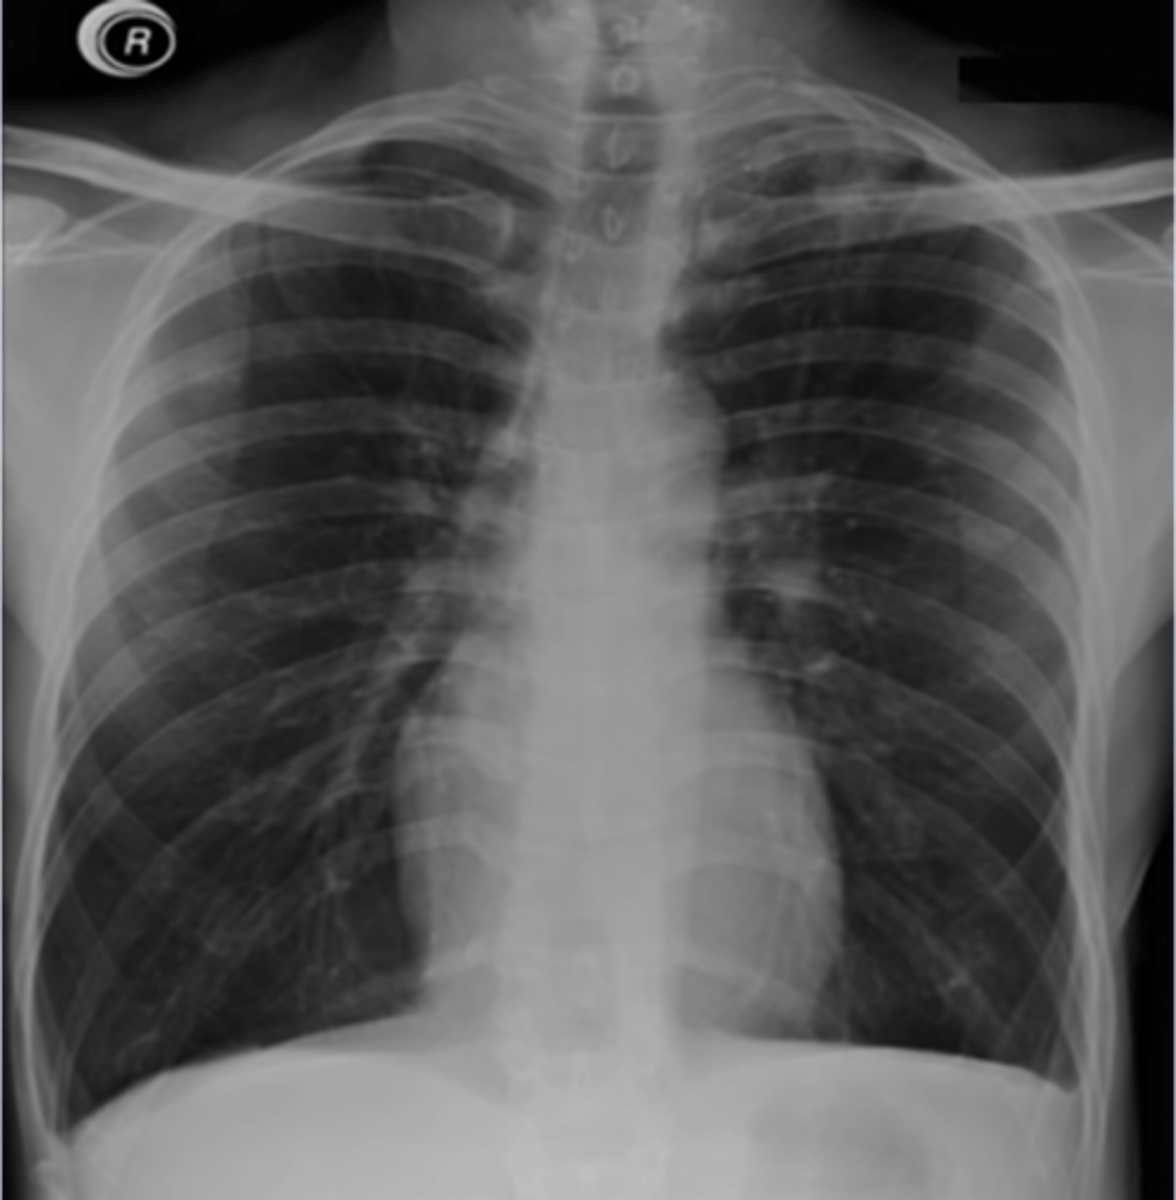

-posteroanterior view -goes from back to front

PA view

-projection: is it in AP or PA view

-most are PA (AP will be labeled)

What does the P stand for in RIPE